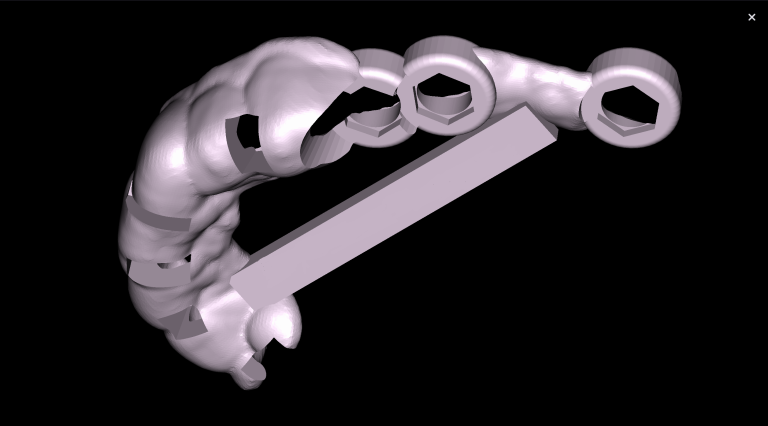

The 3D-Viewer allows the clinician to align the axes according to the area of interest and to study root canal morphology and anatomy before starting a treatment